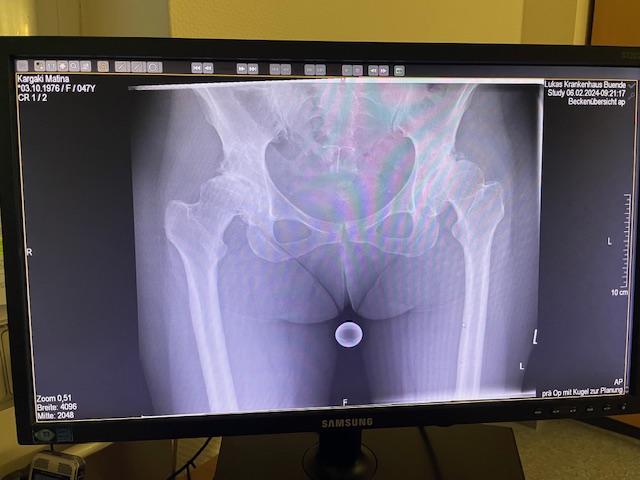

Η ασθενής είχε απευθυνθεί από χρόνια σε πολλούς συναδέλφους ορθοπεδικούς στην Ελλάδα και το εξωτερικό. Είχε προηγηθεί ήδη διεξοδικός απεικονιστικός έλεγχος (ακτινογραφίες λεκάνης και ισχίου, αξονική και μαγνητική τομογραφία).

Διαπιστώθηκε πως η ασθενής έπασχε από δυσπλασία ισχίων άμφω, με το αριστερό ισχίο να υπερισχύει σε συμπτώματα πόνου και περιορισμού της κίνησης.

Το 2024 όταν πλέον η ασθενής απευθύνθηκε σε εμένα, ακολούθησε εκ νέου ακτινογραφικός έλεγχος ώστε να μπορέσει να πραγματοποιηθεί ο προεγχειρητικός ψηφιακός σχεδιασμός του Χειρουργείου.

Ο ακτινογραφικός έλεγχος έδειχνε προχωρημένες εκφυλιστικές αλλοιώσεις και αλλοίωση της ανατομίας της κοτύλης και του μηριαίου.